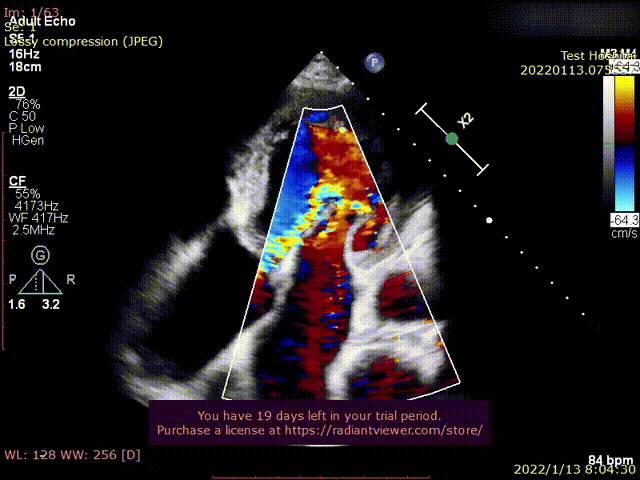

术后超声1

术后超声2